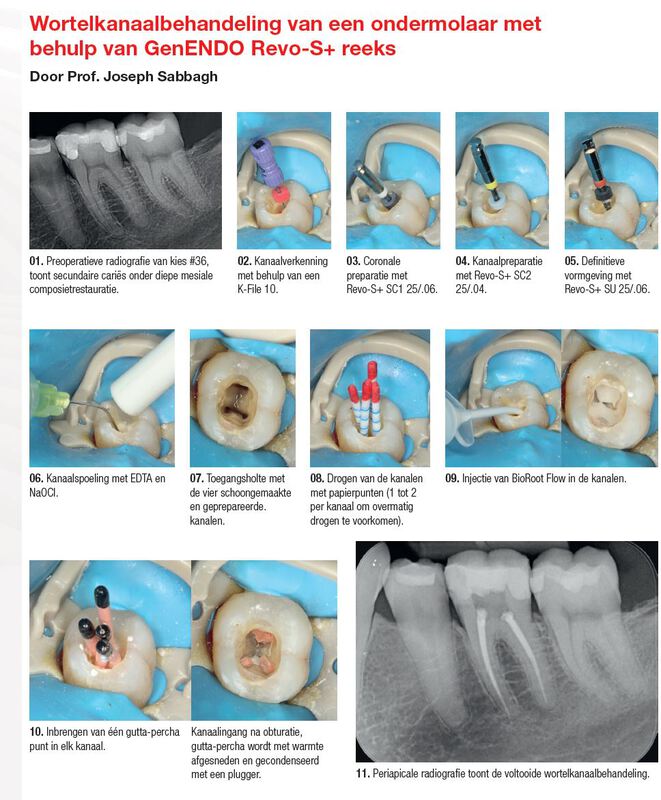

GenENDO Revo-S+ / 3-vijl reeks / 2 verschillende doorsneden / Steriel

Vereenvoudigd protocol, zonder compromis:

- Revo-S+: een korte reeks roterende vijlen

- Weinig stappen

- Snelle procedure

Betrouwbare vijlen voor veilige resultaten:

Exclusief C.Wire warmtebehandeling voor:

- meer flexibiliteit

Vermindert onregelmatigheden

Betere breukbestendigheid

- Weerstand tegen cyclische vermoeidheid

Beperkte risico's op:

- Breuk*

- Vormafwijking kanaal**

- Schroefeffect**

* GenENDO Revo-S+, GenENDO Glider en GenENDO Remover

**GenENDO Revo-S+ en GenENDO Glider